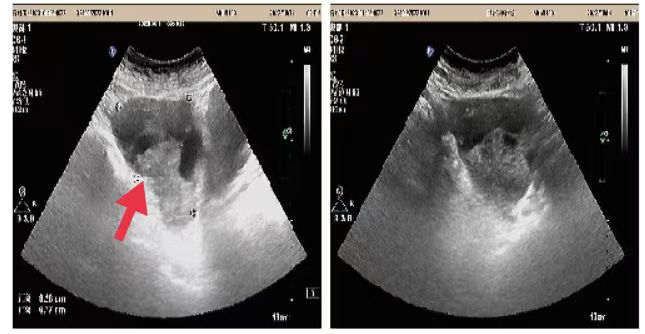

03、**男士,73岁

于2023年10月3日在邯郸仁泰北区体检。实验室检查提示:前列腺特异抗原(PSA)23.17 ng/ml。前列腺彩超检查提示:前列腺稍大,实质回声欠均匀,内可见稍低回声,大小约1.3*1.6cm,边界欠清,内回声欠均匀,CDFI:可见点状血流信号,建议客户到三甲医院进一步检查。2023年10月17日电话回访,客户家属告知,已到三甲医院进一步检查等待结果,2023年10月29日跟踪回访,客户家属告知,客户已在省某三甲医院手术治疗。